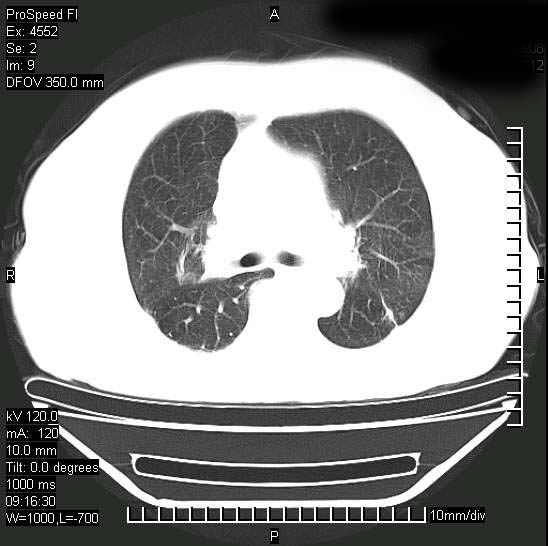

标题: CT15528:女性,79岁,近几日晚上高热,39度,仍咳少量血 [打印本页]

十几年前曾患肺结核,一周前突咳血约100ml,中性粒细胞稍高,诊断两上肺陈旧结核,下肺炎症,给予抗炎治疗,近几日晚上高热,39度,仍咳少量血,4天前ct及今天ct上传。

[face=黑体]8月30日[/face]

支持陈旧性肺结核并两下肺感染,两侧胸腔积液。

短短几天内,病变范围明显增多扩大,以左侧明显,而且双侧出现胸水,还是考虑感染.

支持  结核ban感染,节段性肺不张,支气管内膜结核可能

1)两肺结核并感染。2)不排除左肺上叶中央型肺癌并阻塞性肺炎、肺不张可能;建议行纤支镜检查。3)右肺门及纵隔淋巴结肿大。4)双侧胸腔积液。